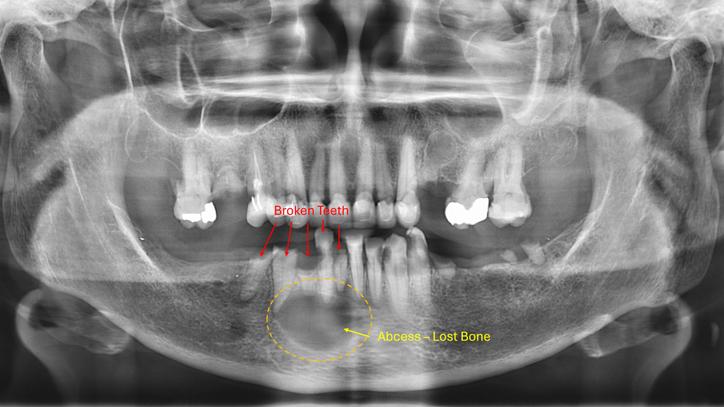

Dental abscesses are serious infections that form around the root of a tooth. If untreated, they can spread to the jawbone or bloodstream. We recently saw a patient who delayed treatment for broken teeth — the infection became chronic, weakening her lower jaw and requiring urgent surgery from an oral maxillofacial surgeon. Broken or abscessed teeth should never be ignored; removal is often the only way to stop the infection and prevent life-altering complications.

bone loss.jpg

Leaving broken teeth in the mouth can lead to severe complications when left untreated.

Teeth broken below the gumline or beyond repair may need removal. If left untreated, fragments can harbour bacteria and cause chronic infection — as in the urgent case mentioned above.